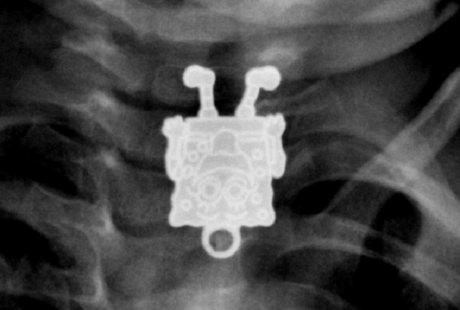

Setelah tubuhnya di-scanning, Dr Ghofran Ageely mengatakan dari hasil scan pertama, ia hanya melihat ada sesuatu yang kecil dan tipis yang terperangkap di dalam esofagus atau kerongkongannya. Hasil scan tersebut memang hanya memperlihatkan kondisi tubuh si anak dari samping.

"Saya kira itu pin atau aksesoris rambut, tapi ketika saya melihat hasil scan dari depan, saya terkejut karena jelas-jelas ada SpongeBob di sana," ungkap Dr Ageely seperti dikutip dari Live Science, Senin (26/1/2015).

Radiologis dari King Abdulaziz University Hospital, Jeddah ini semakin terpana karena meskipun hanya hasil scan, gambar SpongeBob yang diperlihatkan di sana sangatlah detail. "Saya bisa melihat ekspresi wajahnya, sepatunya, dan jari-jarinya. Lengkap dengan senyum dan lidahnya yang menjulur keluar. Luar biasa!" imbuhnya.

Setelah ditelusuri ternyata benda berbentuk SpongeBob itu tak lain liontin dari kalung milik kakak si balita. Beruntung liontin itu dapat diambil dari kerongkongan si anak tanpa meninggalkan komplikasi apapun.

Namun Dr Ageely mengaku belum pernah melihat ada benda yang bisa terlihat dengan detail semacam itu dari hasil scan. Untuk itu ia memutuskan membagi kasusnya lewat situs Radiopaedia. org, forum diskusi antarradiologis dan mahasiswa kedokteran untuk membahas tentang benda-benda asing yang pernah masuk ke dalam tubuh manusia.

Menurutnya, wajah SpongeBob bisa terlihat dengan jelas dari hasil scan karena karakter tersebut diukir secara langsung di atas logam.